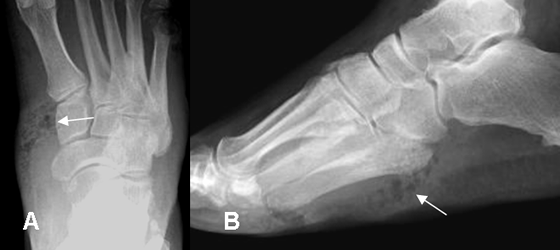

Fig 14. Fasceitis necrotizante.

A: Rx AP y B: Rx lateral. Edema de tejidos blandos en la parte interna del mediopié, con burbujas de aire por fasceitis necrotizante.